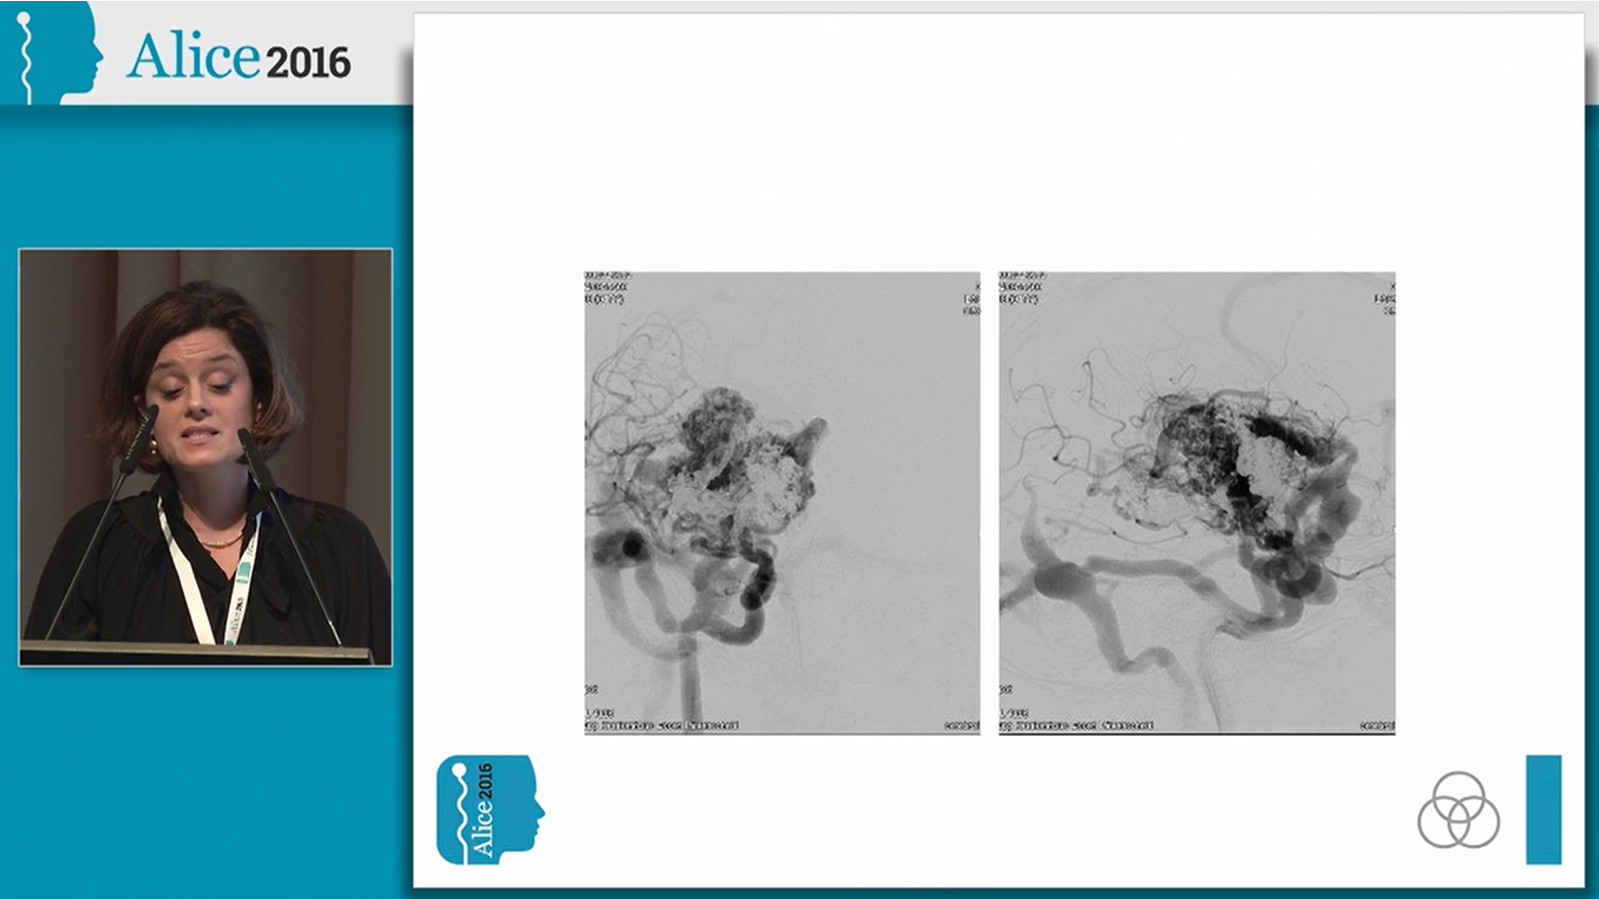

Ruptured hypothalamic AVM treated by transarterial embolization with PHIL